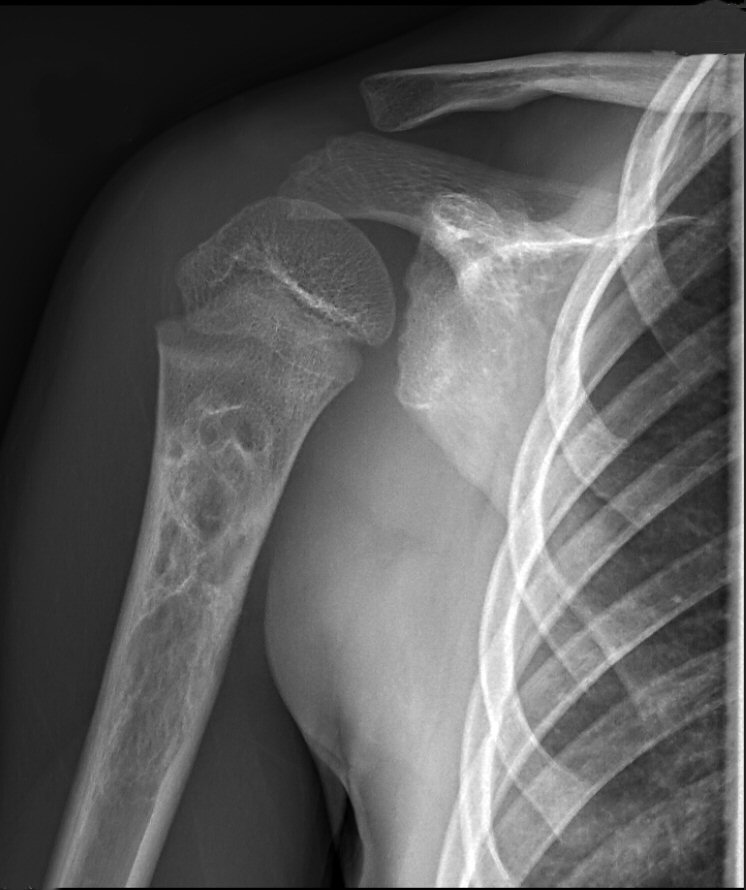

Aneurysmal bencysta lateralt i nyckelben